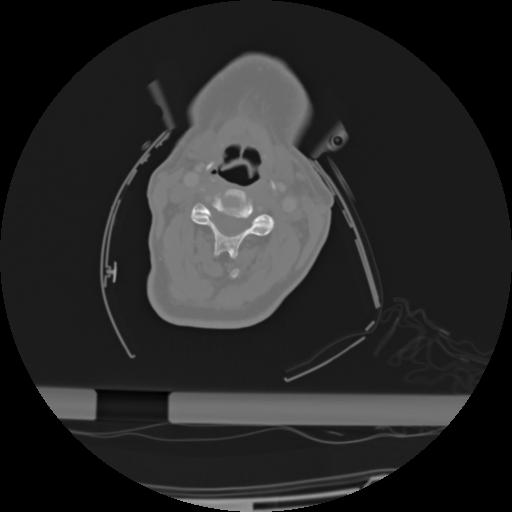

21 ANGIO,CE,Axial,3.0,ANGIO,,